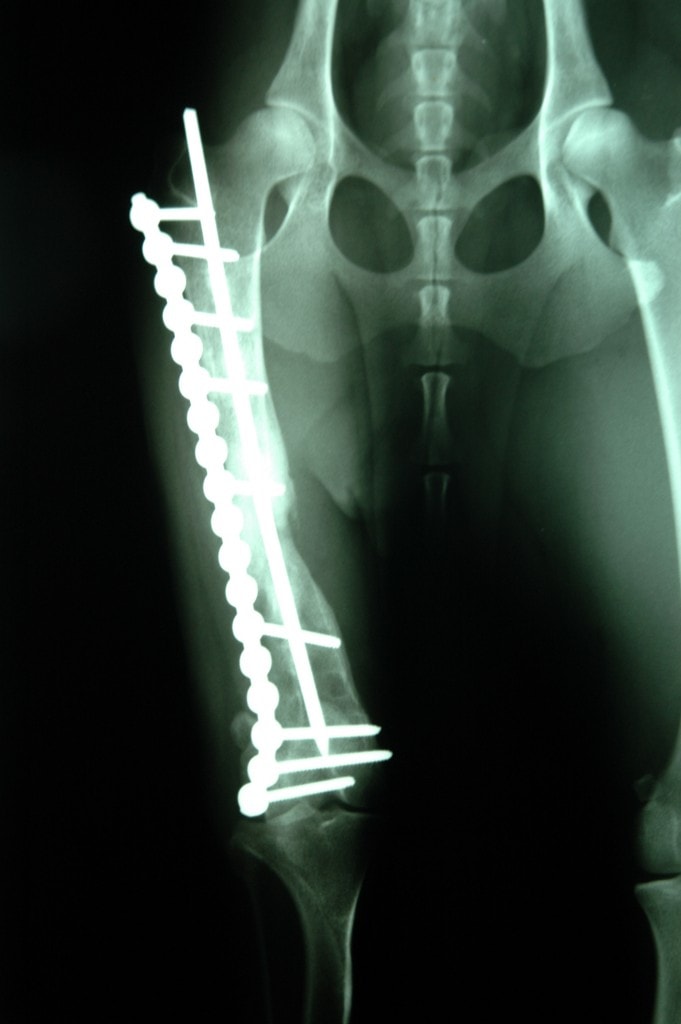

Unsere 1,5 Jahre alte Border Colli Mix Hündin „Sunny“ hat einen langen Leidensweg hinter sich. Nach einem Unfall war ihr Bein gebrochen. Durch verpfuschte Operationen war Sunny kurz davor, ihr Bein zu verlieren. Ihrem Besitzer waren die Behandlungskosten zu viel und so wurde sie bei uns abgegeben. Durch eine aufwendige Operation konnte ihr Bein gerettet werden. Noch ist viel Physiotherapie nötig, damit Sunny ihr Bein wieder voll belasten kann.